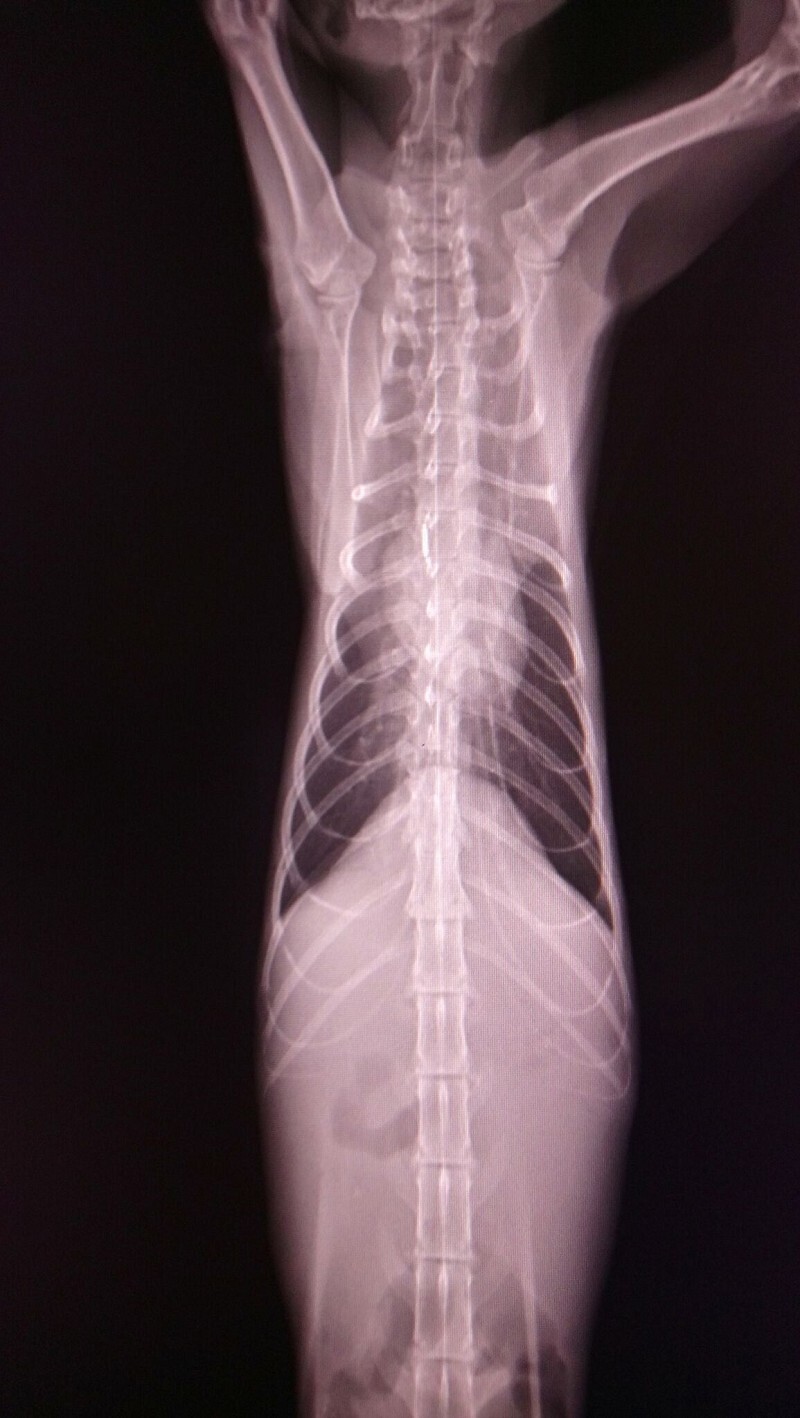

經醫師檢查發現瘦瘦有中度貧血.白血球極度偏高.黃疸.肝指數輕微偏高

也是愛滋感染的貓咪

超音波檢查發現腎腫大且大部分病灶都在腎臟皮質處.有少量腹水動物近況說明: 住院治療前醫師就有說貓咪狀況不樂觀

醫師診斷是乾式腹膜炎,離開我們只是時間早晚問題。